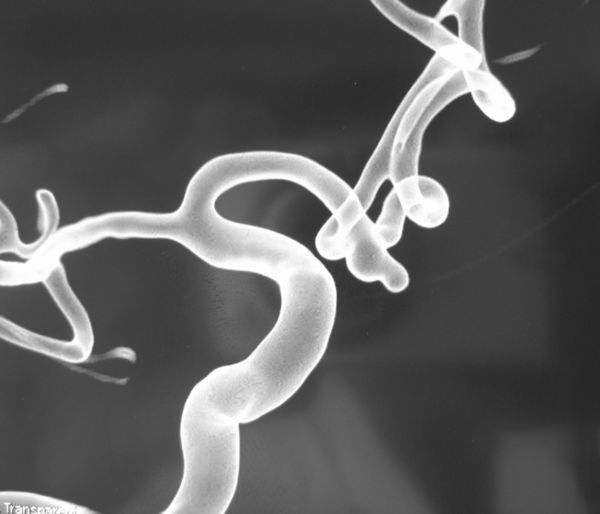

病例2、微小动脉瘤栓塞:女性,52岁,基底动脉顶端微小动脉瘤破裂出血,动脉瘤大小约1.5X1mm,位置深,周围重要结构多,手术夹闭困难,经全科医生认真分析,决定采取支架辅助+弹簧圈栓塞的方法,介入栓塞治疗,3月18日,孟祥靖主任在介入科、麻醉科的大力配合下,栓塞取得圆满成功,目前患者已痊愈出院。

病例2:基底动脉顶端微小动脉栓塞术前、后